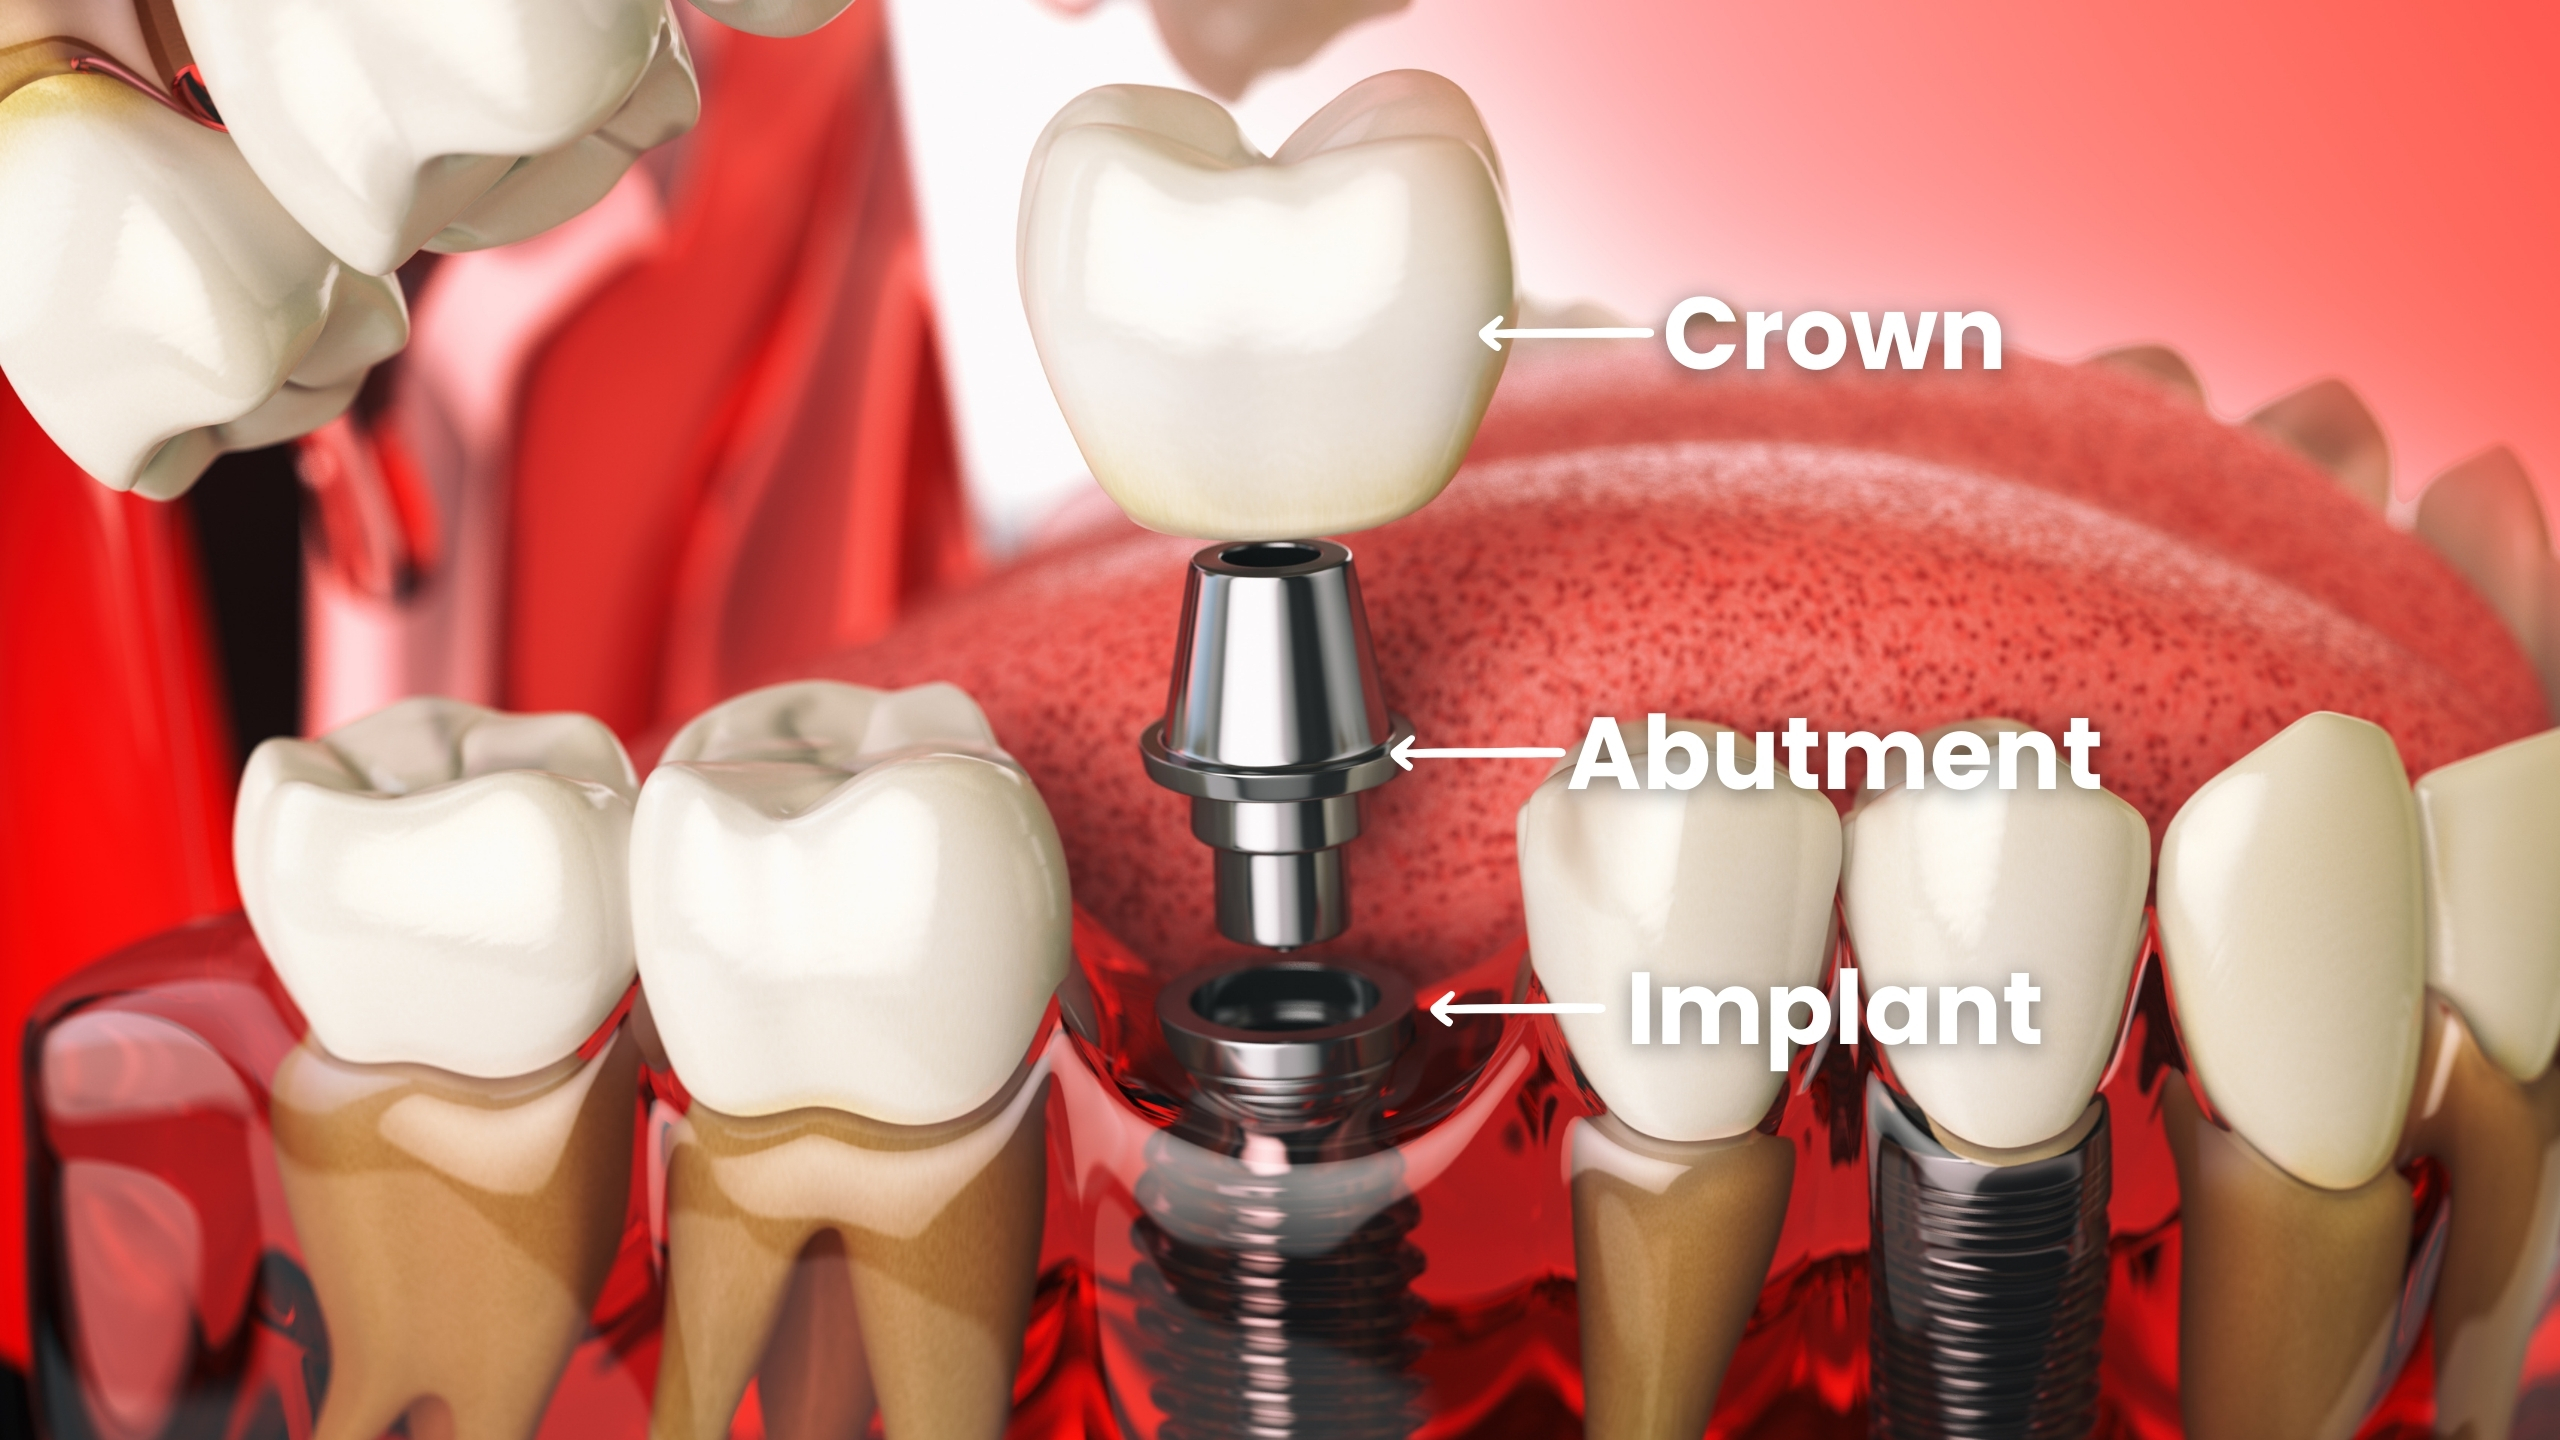

Early-stage gum disease (gingivitis) can often be managed with a professional cleaning and improved home care. More advanced disease may require scaling and root planing, surgical pocket reduction, or regenerative procedures. The sooner you come in, the more options are available — and the more of your natural teeth we can preserve.